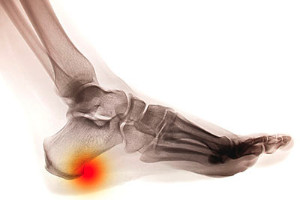

What is a Common Source of Heel Pain?

One common cause of heel pain is a foot condition known as a heel spur. With this condition, it’s common to notice redness and swelling around the affected heel. A heel spur is defined as a bone growth found in the heel, and it’s typically diagnosed by having an x-ray performed. The pain felt with this condition is usually noticed when one is walking, running, jogging, or partaking in other physical activities. To help ease the discomfort of this condition, it may be beneficial to rest the affected foot and to apply a cold compress on the heel. If you’re experiencing extreme pain in your heel, it’s important to get a professional diagnosis. It’s suggested that you speak with a podiatrist to help advise you on a proper treatment plan.

Heel spurs can be incredibly painful and sometimes may make you unable to participate in physical activities. To get medical care for your heel spurs, contact Roy Moeller, DPM from Foot & Ankle Physicians West. Our doctors will do everything possible to treat your condition.

Heels Spurs

Heel spurs are formed by calcium deposits on the back of the foot where the heel is. This can also be caused by small fragments of bone breaking off one section of the foot, attaching onto the back of the foot. Heel spurs can also be bone growth on the back of the foot and may grow in the direction of the arch of the foot.

Older individuals usually suffer from heel spurs and pain sometimes intensifies with age. One of the main condition's spurs are related to is plantar fasciitis.

Pain

The pain associated with spurs is often because of weight placed on the feet. When someone is walking, their entire weight is concentrated on the feet. Bone spurs then have the tendency to affect other bones and tissues around the foot. As the pain continues, the feet will become tender and sensitive over time.

Treatments

There are many ways to treat heel spurs. If one is suffering from heel spurs in conjunction with pain, there are several methods for healing. Medication, surgery, and herbal care are some options.

If you have any questions feel free to contact our office located in Edina, MN . We offer the latest in diagnostic and treatment technology to meet your needs.